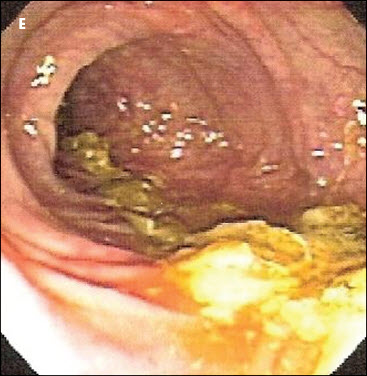

At our advice, the patient—who was taking 16 medications in total— discontinued aspirin therapy. Thereafter, the patient’s health improved and a diagnosis of NSAID-induced colitis was made. CT (D) and colonoscopy (E) done 6 months later showed complete resolution of the lesion. Our patient is currently controlling her arthritic joint pain with acetaminophen.